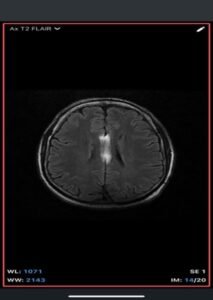

Imaging Findings-

- MRI

- T1-weighted: Hyperintense (fat signal).

- T2-weighted: Variable, usually hyperintense; may show chemical shift artifacts.

- Fat-suppressed sequences: Complete signal suppression confirms fat composition.

- Post-contrast: No enhancement.